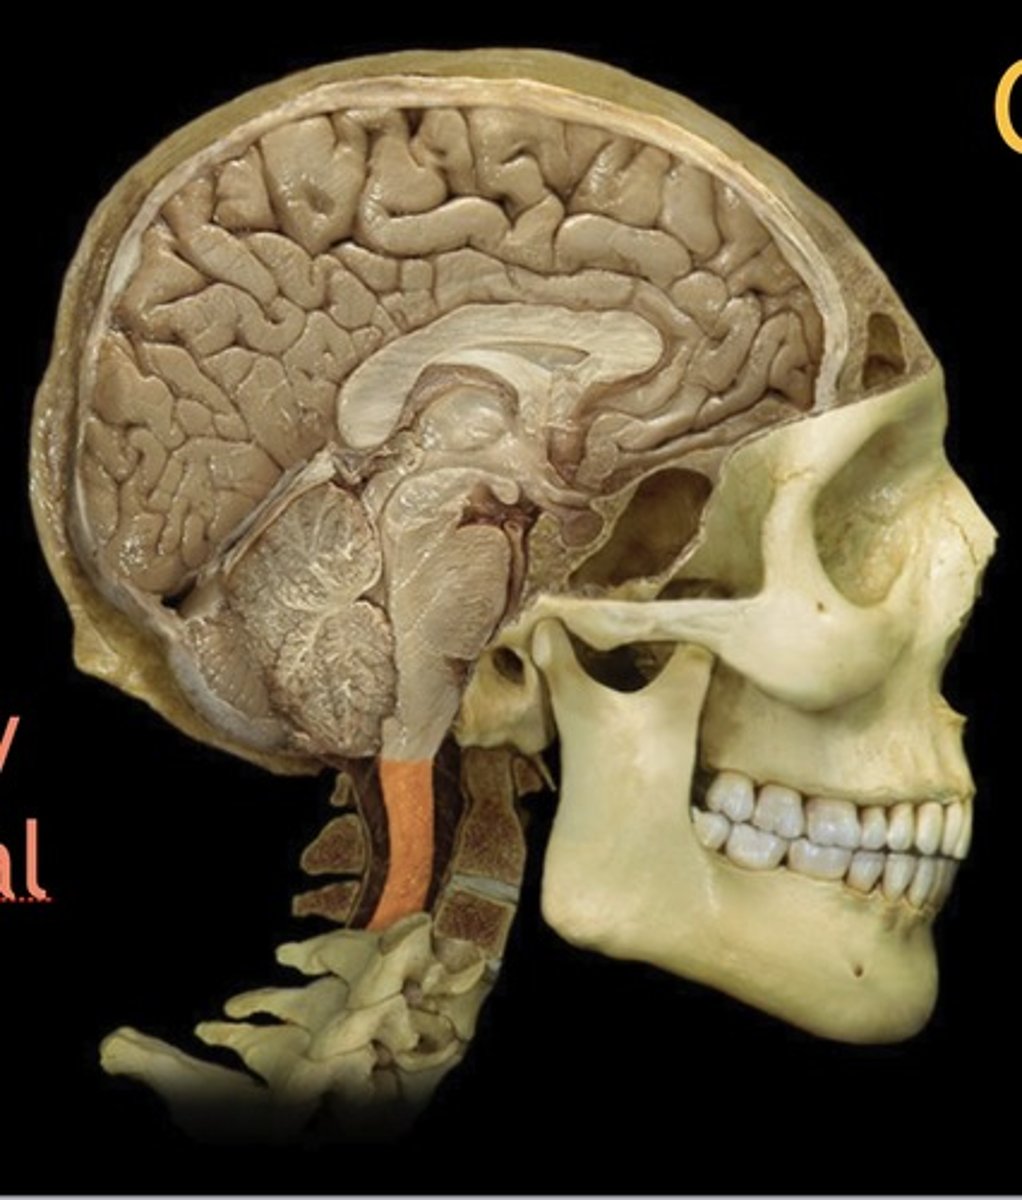

brainstem

Name this structure

Midbrain

Name this structure

Pons

Name this structure

Medulla Oblongata

Name this structure

Cervical Spinal Cord